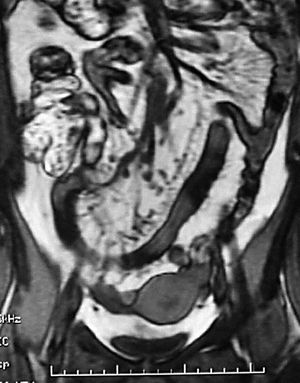

Los hallazgos en la TC y la RM sugestivos de EC en fase activa son la hiperemia, característica de un proceso inflamatorio y la estratificación de la pared intestinal (fig. 8). El concepto de hiperemia que depende de la prominencia, tortuosidad y dila-tación de los vasa recta, se traduce por el signo del "peine" (fig. 9), descrito por Meyers y McGuire16 en estudios tomodensitométricos de pacientes en fase activa de la EC. Si bien no es un signo patognomónico de la EC, la hiperemia a nivel de las asas intestinales es marcador de actividad17. La estratificación de la pared intestinal justifica un aspecto en "diana" (fig. 3B) con una zona de alto valor de atenuación interna que corresponde a la mucosa, otra zona también de alto valor de atenuación periférica que corresponde a la muscular-serosa y una zona intermedia entre ambas, de menor valor de atenuación que corresponde a la submucosa edematosa en relación con la ectasia linfática12.

Fig. 8.--Ileocolitis granulomatosa. (A) La resonancia magnética (RM) en secuencia potenciada en T1, tras la administración de gadolinio endovenoso, en corte de orientación axial, muestra engrosamiento mural del íleon terminal y del polo cecal que se realza con contraste. (B) Correlación en el plano coronal.

Fig. 9.--Enfermedad de Crohn, fase activa inflamatoria. (A) El signo del peine en la resonancia magnética (RM), secuencia potenciada en T1, imagen de orientación coronal. (B) Secuencia potenciada en T2, corte coronal, muestra prominencia y dilatación de los vasa recta.